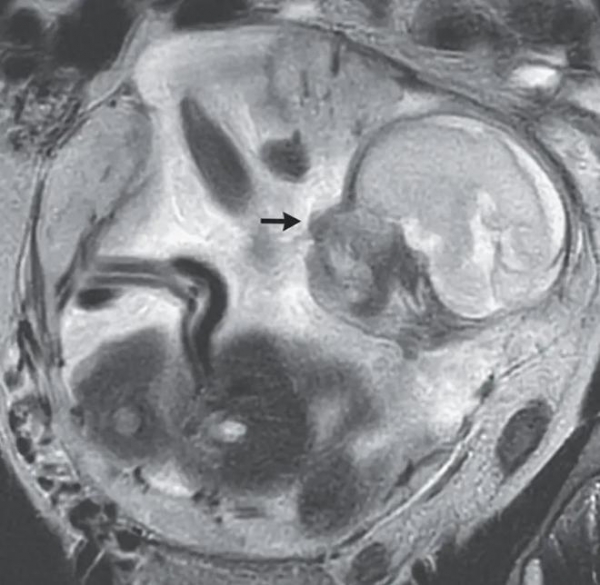

近日,一则法国37岁女子在腹痛腹胀后前往医院检查,竟然发现怀孕23周,而胎儿不在子宫里,竟然在腹腔内的肠道中"安家落户"了。

这种罕见的情况属于"宫外孕",即受精卵并未着床在子宫内,而是在腹腔内。对于这位女性来说,症状一度让人困扰,但经过医生的及时检查,竟发现了这个医学上极为罕见的案例。

宫外孕,尤其是"腹腔妊娠",在所有宫外孕中只占极小比例,更是医学界的一个谜。它对母体的威胁不可小觑,可能导致出血、休克、腹痛等症状,甚至流产的风险。